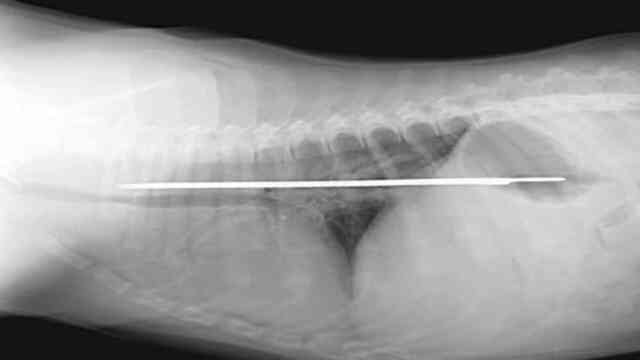

Keep Sharp Objects Away From Curious Puppies

Puppies and toddlers basically require the same precautions—they are both curious and don’t know what is right, wrong, safe, or dangerous. In an ideal world, parents and pet owners would be able to monitor and guide their loved ones on a moment-to-moment basis, but as adults who need to work, do chores and run errands, sometimes dangerous objects are able to slip by.

This is an X-ray of an unfortunate mishap. A five-month-old St. Bernard puppy swallowed a serrated knife. Although the pup was already around 70 pounds, the youngling didn’t realize it wasn’t very nutritious until it was already down his throat. With some surgery and attentive aftercare, the pup survived, and, hopefully, he learned a lesson too.